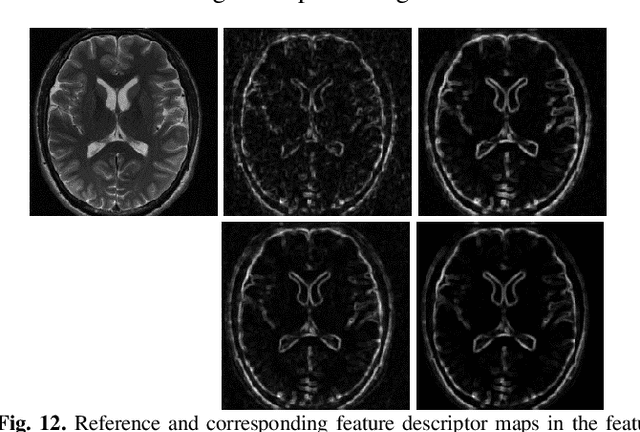

Abstract:To improve the compressive sensing MRI (CS-MRI) approaches in terms of fine structure loss under high acceleration factors, we have proposed an iterative feature refinement model (IFR-CS), equipped with fixed transforms, to restore the meaningful structures and details. Nevertheless, the proposed IFR-CS still has some limitations, such as the selection of hyper-parameters, a lengthy reconstruction time, and the fixed sparsifying transform. To alleviate these issues, we unroll the iterative feature refinement procedures in IFR-CS to a supervised model-driven network, dubbed IFR-Net. Equipped with training data pairs, both regularization parameter and the utmost feature refinement operator in IFR-CS become trainable. Additionally, inspired by the powerful representation capability of convolutional neural network (CNN), CNN-based inversion blocks are explored in the sparsity-promoting denoising module to generalize the sparsity-enforcing operator. Extensive experiments on both simulated and in vivo MR datasets have shown that the proposed network possesses a strong capability to capture image details and preserve well the structural information with fast reconstruction speed.